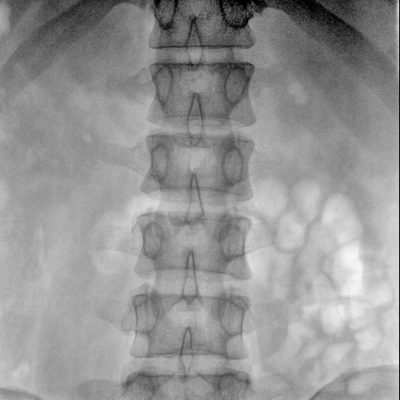

骨科: 經(jīng)皮錐體成形術(shù)、經(jīng)皮椎間盤臭氧治療術(shù)、胸脊椎固定、骨活檢、腰椎內(nèi)固定術(shù)等。